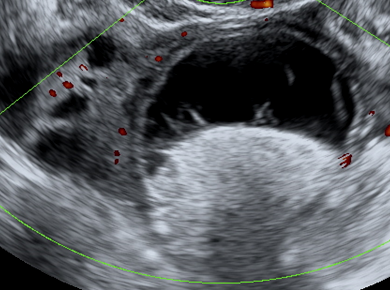

Synes du denne cysten ser veldig skummel ut? Mange fjerner slike cyster "for sikkerhets skyld" og fjerner mye frisk vev, fordi de er usikker hva de har med å gjøre. IOTA-klassifikasjonen kan hjelpe å ta gode kliniske avgjørelser- men du må være trygg og sertifisert før du begynner å bruke den.